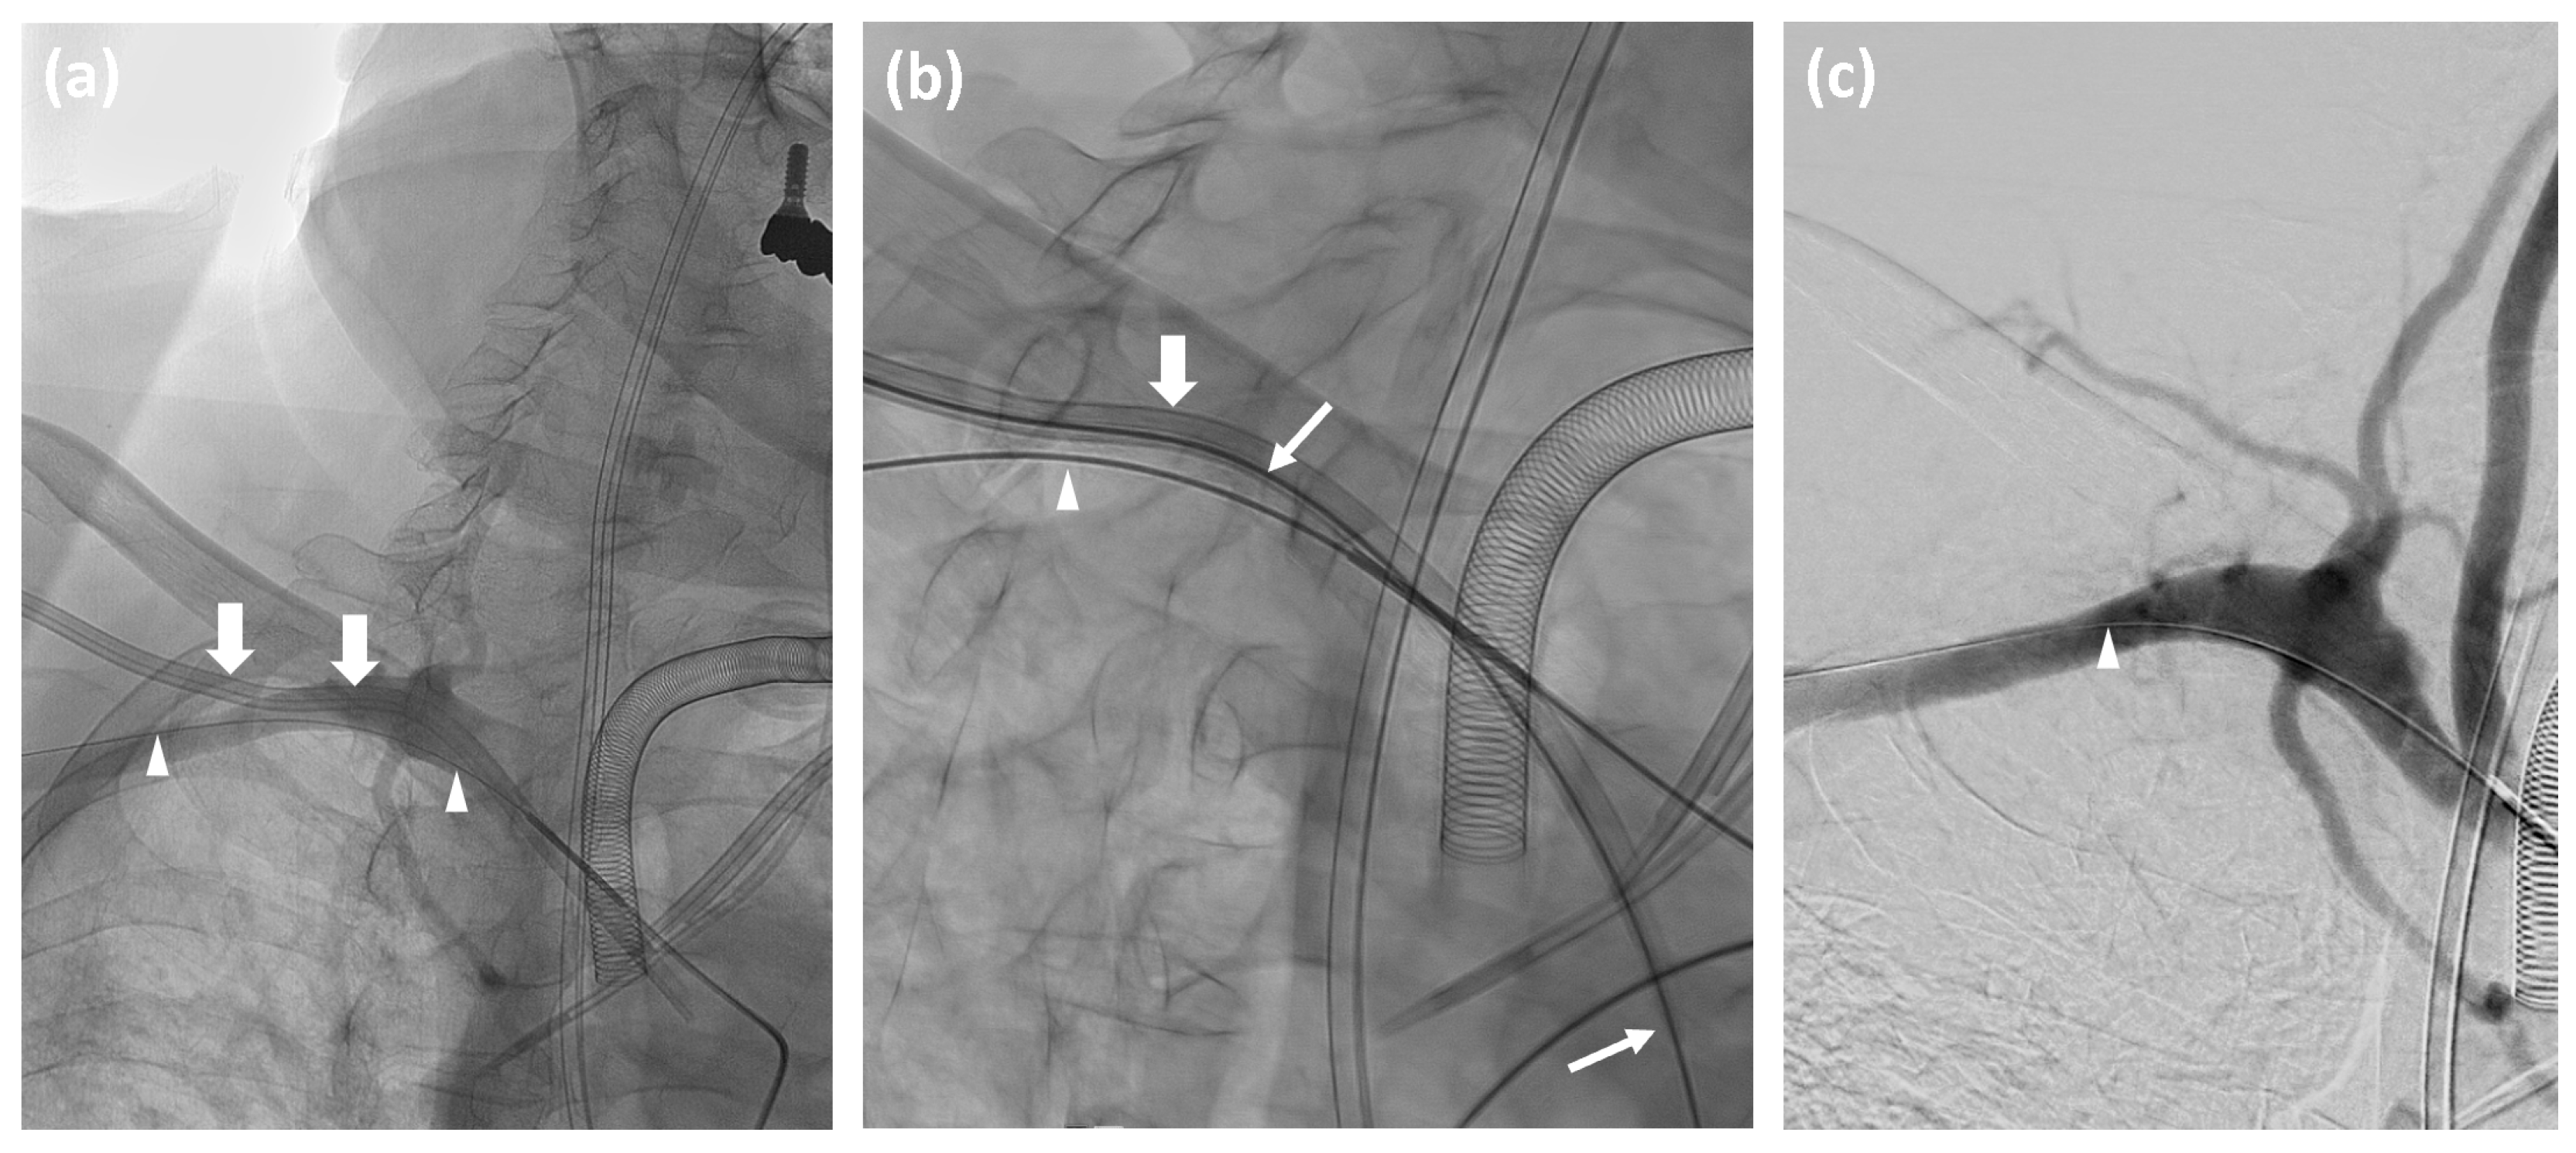

- Advance a catheter in the affected subclavian artery and perform angiographic contrast series in at least two projections to visualize the exact position of the misplaced catheter or the presence of any complications such as dissection or hemorrhage.

- Measure the vessel diameter and prepare an appropriate angioplasty balloon in the angio-suite as a precautionary measure.

- Insert an Amplatz wire into the misplaced catheter, and then remove the catheter.

- Depending on the catheter’s diameter, deploy a 6F or 8F Angio-Seal™ vascular closure device according to the manufacturer’s instructions.

- Conduct a follow-up angiographic series to confirm successful closure.

- If hemorrhage or pseudoaneurysm is detected, inflate the prepared angioplasty balloon for at least three minutes. For persistent hemorrhage, deploy an appropriately sized stentgraft, taking care to preserve the vertebral artery origin.